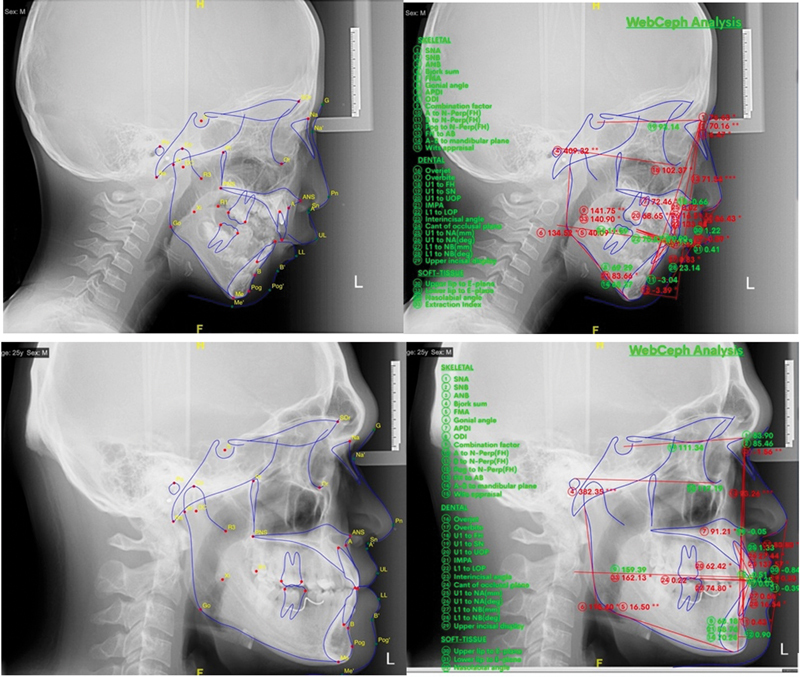

Methods: This study used a case-control design conducted during March to September 2024 at Dr. Hasan Sadikin Hospital, Bandung, on subjects aged 7 to 23 years who were divided into two groups, namely mouth breathing and nasal breathing. Data were obtained from filling out the MBD-MBS (Mouth Breathing in Daytime and Mouth Breathing during Sleep) questionnaire, taking lateral cephalometric photographs, and cephalometric measurements using the WebCeph application. Statistical analysis was performed with SPSS software using the chi-square and Mann-Whitney tests.

Results: There were significant differences in angular parameters between the two groups, namely the Sella-Nasion to Gonion-Gnathion (SN.GoGn) angle ( p  = 0.029), the Frankfort mandibular angle (FMA; p  = 0.023), and the mandibular plane to palatal plane (MP.PP) angle ( p  = 0.012); the Articulare-Gonion-Menton (ArGoMe) angle was greater in the oral breathing group ( p  = 0.003). The linear parameter values in both groups were not different ( p  > 0.05).

Conclusion: Mouth breathing affects facial anthropometry, resulting in an increase in retrognathic mandibular and maxillary angles.